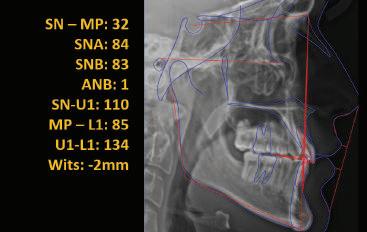

20 Dental Tribune Bulgarian Edition / октомври 2022 г. П ациентите със завършен растеж и скелетни проблеми обикновено представляват предизвикателство за ортодонт ската практика. Необходимостта от изваждане на зъби в комбинация с особеностите на възрастовата ортодонтия изисква особено внима ние. Фокусът върху критично важното значение на позицията на долните резци във връзка с дългосроч ната стабилност и постигането на оптимални оклузални взаимоотношения при затварянето на екстракционните пространства лесно може да излезе извън контрол. Когато към тези чисто кли нични проблеми се добави и стресът от натоваре ната практика, предизвикателството става още по-голямо. Всички тези фактори налагат използ ването на доказан подход с ясни и последовател ни стъпки, в което се разкрива силата на дисциплината „Алекзандър“ – предвидим протокол през целия процес на елиминиране на ротациите, ниве лиране на дъгите, затваряне на екстракционните пространства и финализиране на случая. Именно такъв е и случаят, който презентираме –екстракционен, скелетен клас 3 при възрастен па циент, лекуван по системата „Алекзандър“. ПРЕДВИДИМИ РЕЗУЛТАТИ ПРИ ПАЦИЕНТИ СЪС ЗАВЪРШЕН РАСТЕЖ И СКЕЛЕТЕН КЛАС 3, ИЗПОЛЗВАЙКИ ЕКСТРАКЦИОННО ЛЕЧЕНИЕ ПО ДИСЦИПЛИНАТА „АЛЕКЗАНДЪР“ Д-р Радой Димитров, България Преди започване на лечение клиничен случай | ортодонтия Фиг. 1а–1e Преди започване на лечение. Пациентът пристига в практиката с основното оплакване от невъзмож ност за нормално дъвчене. Снета е цялата необходима диагностична ин формация. Фиг. 1f–1h Снимки в профил и анфас. Фиг. 1i–1k Панорамна снимка, телерентгенография и анализ на телерент генография. Фиг. 1а Фиг. 1d Фиг. 1f Фиг. 1g Фиг. 1h Фиг. 1e Фиг. 1b Фиг. 1c Фиг. 1i Фиг. 1j Фиг. 1k

closed.

21Dental Tribune Bulgarian Edition / октомври 2022 г. ДИАГНОСТИЧНИ РЕЗУЛТАТИ: 1. Възраст на пациента: 21 години 2. Скелетен клас III (ANB 0) 3. Зъбен клас 3 4. Ръбцова захапка във фронта, кръстосана в дисталните участъци 5. Тясна горна челюст 6. Overjet – 0 мм, Overbite – 0 мм 7. Несъответствие на горната с долната средна линия 8. Единични контакти в ЦО 9. Хиподивергентен тип на растеж SN/MP – 33.5 10. Неравен гингивален контур 11. Неравна линия на усмивката 12. Тенденция за рецесии в долен фронт ПРЕПОРЪЧИТЕЛНО ЛЕЧЕНИЕ: Пълно ортодонтско лечение с метални брекети „Алекзандър“ Корекция на клас 3 захапката в областта на кучешките зъби с екстракция на първите пре молари в долна челюст Корекция на кръстосаната захапка в дистални участъци Коригиране на ръбцовата захапка във фронта Подобряване на ОJ и OB на пациента Стрипинг в долен фронт Подреждане на зъбите в горната и долната челюст Професионално хигиенизиране и профилактични дентални прегледи са препоръчителни на всеки 6 месеца. 1-ви месец След 1 месец са залепени брекети в горната челюст – поставена е еластична дъга. 016 NiTi. В долната челюст са елиминирани ротациите, поставена е стоманена дъга. 016SS, закалена с ток, и еластична верижка за затваряне на пространствата. 3-ти месец В долната челюст е поставена трета дъга – 17 x 25 NiTi с къси лигатури и верижка

Dental Tribune Bulgarian Edition / октомври 2022 г.22 клиничен случай | ортодонтия 14-и месец В горната и долната челюст са поставени последни стоманени дъга с омега луп и тай бек – 17 x 25 SS с четвъртито сечение. Назначени е ластик за средната линия в комбинация с клас 3 ластик (1/4”, 6 1/2 oz). Контролни рентгенографии 13-и месец Екстракционните пространства са затворени. Направена е контролна панорамна снимка за оценка позицията на корените. Взето е решение за презалепване на брекетите на 12, 22 и пръстените на 36 и 46. 21-ви месец Средната линия в горната и долната челюст съвпадат. Ластиците са спрени. Свалени са пръстените и брекетите в горната и долната челюст, зигзаг ластици не са използвани поради благоприятните оклузални взаимоотношения. Фиг. 11j Ортопантомография в края на лечението. Фиг. 11k Телерентгенография след края на лечението. Фиг. 11l Анализ на телерентгенографията след лечението. Фиг. 11m Последователност на дъгите в горната и долната челюст Фиг. 11n Суперимпозиция на PreOp и PostOp ортопантомографии. 10-и месец Затварянето на пространствата е предвидимо и контролирано, без да се отварят пространства в зъбната дъга. Фиг. 8a Фиг. 8b Фиг. 8c Фиг. 8d Фиг. 8e Фиг. 10a Фиг. 10b Фиг. 10c Фиг. 10d Фиг. 10e Фиг. 9a Фиг. 9b Фиг. 9c Фиг. 9d Фиг. 9e Фиг. 9f Фиг. 11a Фиг. 11f Фиг. 11j Фиг. 11l Фиг. 11m Фиг. 11n Фиг. 11k Фиг. 11g Фиг. 11h Фиг. 11i Фиг. 11b Фиг. 11c Фиг. 11d Фиг. 11e

Dental Tribune Bulgarian Edition / октомври 2022 г. 23клиничен случай | ортодонтия реклама Лечението е продължило 21 месеца. Проведено е домашно избелване с индивидуални шини. За автора: Д-р Радой Димитров завършва с отличие Факултета по дентална медицина към МУ–София през 2015 г. В продължение на 5 години работи в няколко водещи практики в София, като през 2019 г. заедно със своята съпру га д-р Траяна Димитрова основават собствена практика в гр. Гоце Делчев –Dimitrovi Dental Care. Посещава редица курсове за повишаване на квалификаци ята, но най-сериозен тласък в развитието на ортодонтската си практика получава след завършването на комплексната ортодонтска програма, воде на от д-р Иван Горялов, базирана на дисциплината „Алекзандър“ – система с повече от 50 години опит в целия свят. Д-р Димитров е член на Българския изследователски клуб „Алекзандър“. Взе ма участие като гост-лектор в симпозиума с международно участие The Power of the Alexander Discipline, който се проведе на 14–15.05.2022 г. С д-р Ди митров можете да свържете на тел. +359885 252 025. Заключение Представеният случай е ярък пример за възможностите и красо тата на дисциплината „Алекзандър“ – приложен е утвърден под ход с ясни правила и са постигнати очакваните цели. Резулта тът ще бъде дългосрочно стабилен, тъй като са спазени всички правила, които се отнасят към максимално комфортната пози ция на зъбите в края на лечението. Постигнати са красива усмив ка и стабилна оклузия. ПОСТИГНАТИ РЕЗУЛТАТИ ОТ ЛЕЧЕНИЕТО 1. Коригирана ръбцова захапка 2. Коригирана клас 3 захапка в областта на ку чешките зъби 3. Коригирана кръстосана захапка в дисталните участъци 4. Коригиран овърджет и овърбайт 5. Разширена е горната зъбна дъга 6. Подредени зъби в горната и долната челюст 7. Постигната е стабилна захапка с множество контакти в ЦО 8. Драматично е подобрена дъвкателната функ ция 9. Подобрена е линията на усмивката ДРУГИ ПРОВЕДЕНИ ДЕНТАЛНИ ПРОЦЕДУРИ 1. Домашно избелване на зъбите 2. Екстракция на мъдреците Фиг. 12a Фиг. 12b Фиг. 12c Фиг. 12eФиг. 12d Фиг. 12f Фиг. 12g Информация за дати, цени и отстъпки www.bracescourses.com 0889 22 55 01 Практически курсове лектор д-р Иван Горялов Дисциплината „Алекзандър“ ПЪТЯТ КЪМ СУПЕРУСМИВКИТЕ 100% връщане на цялата сума, ако не сте удовлетворени след преминаване на Ниво 1 Директно и индиректно залепяне на брекети Анализ, диагноза и план на лечение Лечение на клас 2 дълбока захапка Екстракционно лечение Лечение на клас 3 отворена захапка НИВО 5НИВО 1 НИВО 2 НИВО 3 НИВО 4